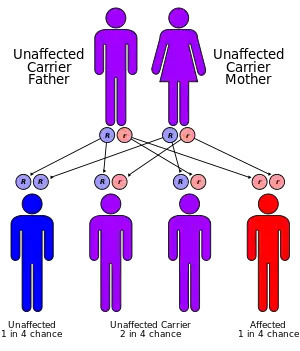

Wilson's disease is caused by a mutation in the Wilson disease protein (ATP7B) gene. This protein transports excess copper into bile, where it is excreted in waste products. The condition is autosomal recessive; for people to be affected, they must inherit a mutated copy of the gene from both parents. Diagnosis may be difficult and often involves a combination of blood tests, urine tests and a liver biopsy. Genetic testing may be used to screen family members of those affected.[1]

The condition is inherited in an autosomal recessive pattern. To inherit it, both of the parents of an individual must carry an affected gene. Most have no family history of the condition.[15] People with only one abnormal gene are called carriers (heterozygotes) and may have mild, but medically insignificant, abnormalities of copper metabolism.[14]